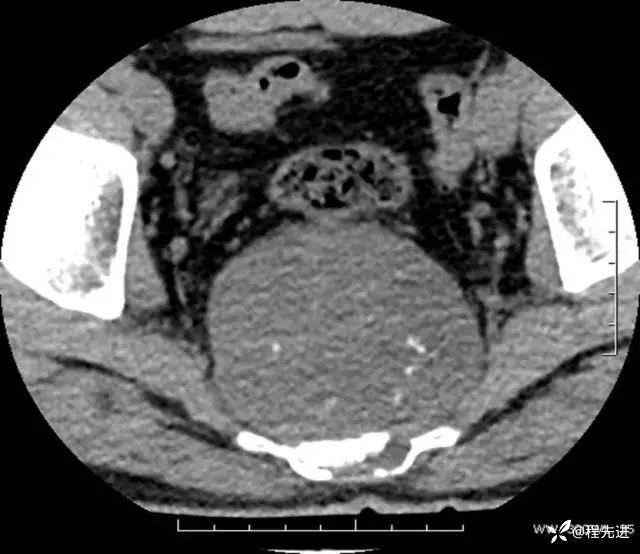

CT平扫:

软组织窗: